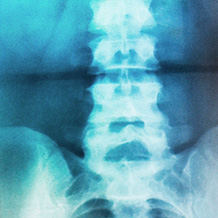

Um ein Maximum an Information bei möglichst geringer Strahlenbelastung zu bekommen, arbeiten wir mit einer modernen, digitalen Röntgenanlage und Bildverarbeitung. Der große Unterschied zum herkömmlichen Röntgenfilm ist auch die bessere Nachbearbeitung und genaue Beurteilung der Untersuchung sowie die Integration durch digitale Vernetzung.

Das Röntgenbild steht in jedem Behandlungszimmer zur Verfügung. Unsere Mitarbeiterinnen im Röntgenbereich sind in Fortbildungen speziell geschult und besitzen Qualifikationen im Strahlenschutz.